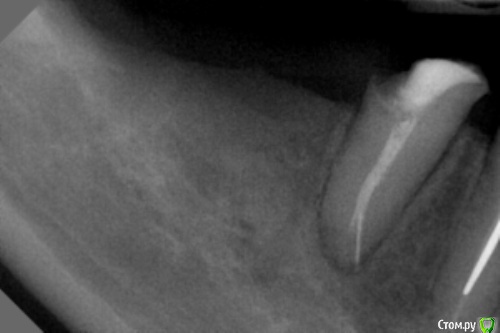

dr.Dre Опубликовано 15 октября, 2016 Поделиться Опубликовано 15 октября, 2016 Добрый день коллеги,реально ли извлечь инструмет,в наличии есть бинокуляры ,какими методиками посоветуете? Ссылка на комментарий

Stom22 Опубликовано 19 октября, 2016 Поделиться Опубликовано 19 октября, 2016 (изменено) Тут велика вероятность при извлечении инструмента протолкнуть его за апекс. Лучше там его и оставить. Из двух зол выбирать надо меньшее. Пациенту объяснить, что зуб не гарантийный, "сколько послужит - столько послужит", у некоторых такие зубы по 10 лет стоят без симптоматики. И по снимку не очень понятно, кажется ложный ход создан инструментом, если так, то это уже хуже и может развиться симптоматика. Изменено 19 октября, 2016 пользователем Stom22 Ссылка на комментарий

dr.Dre Опубликовано 4 ноября, 2016 Автор Поделиться Опубликовано 4 ноября, 2016 Вопрос был о технической стороне дела, но не в ней дело, а в том, надо ли вообще его извлекать? Что с зубом, почему пришел, что за инструмент, когда там очутился, при каких условиях и т.д. и т.п.нужно извлекать пациент жалуется на боли,зуб обтурирован года 2 говорит пациент Ссылка на комментарий